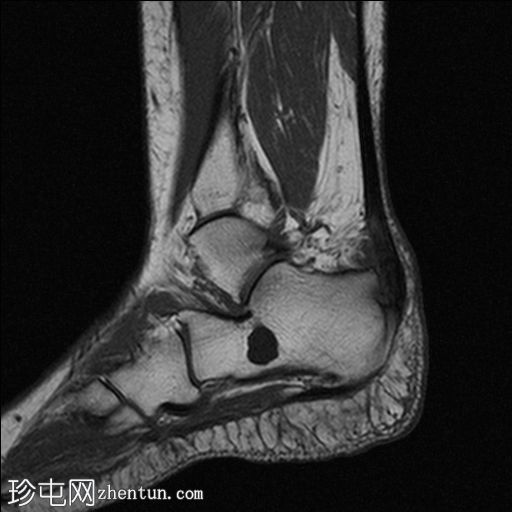

矢状面

T1

跟腱远端1/3信号强度增高且增厚,提示跟腱病变。

跟腱远端部分撕裂

跟腱前滑囊积液导致扩张,提示滑囊炎。

跟骨后部骨刺提示 Haglund 畸形。

跟骨隆突后部局部中度骨髓水肿,周围脂肪组织。

其他发现包括跟骨骨刺和跟骨囊肿。